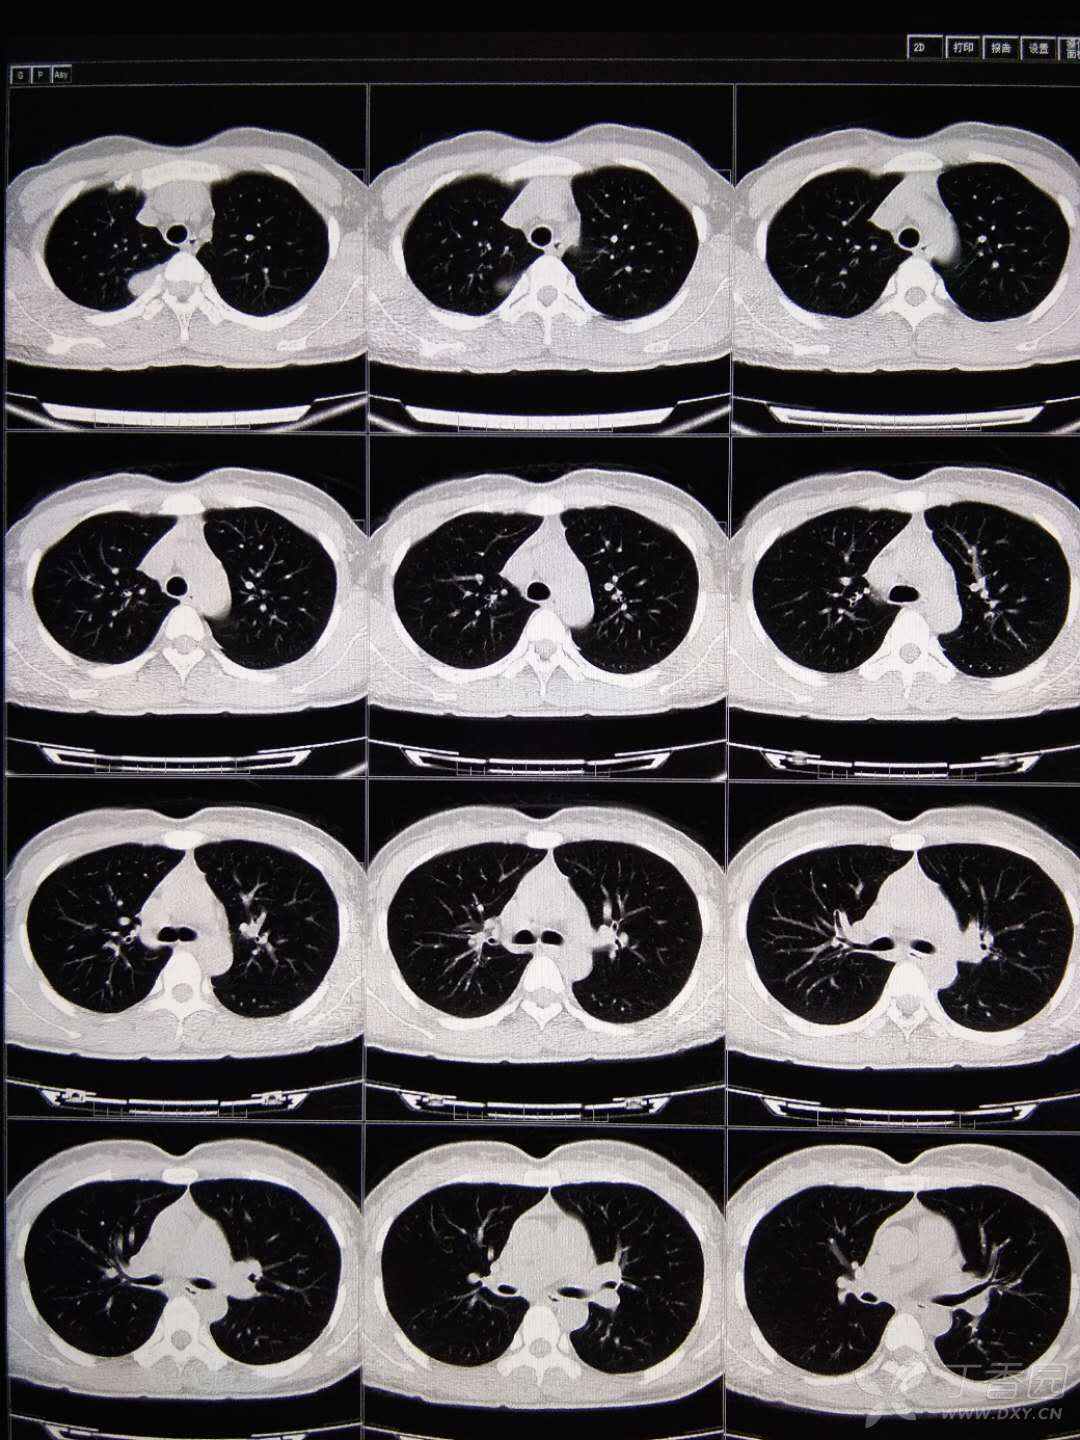

图3-22 原发性结核,肺内病灶及肺门增大,呈"哑铃状"图3-23 血行播散型

各型肺结核的典型影像表现